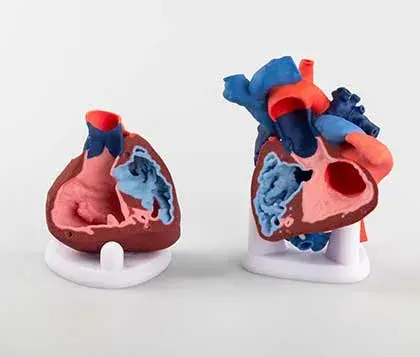

Since each patient's anatomy is different, patient-specific anatomic models provide an opportunity to visualize and plan surgeries prior to entering the operating room. In addition, you can use anatomic models to educate patients and their families on an upcoming procedure.

Full-color anatomic models to aid in visualization of complex structures